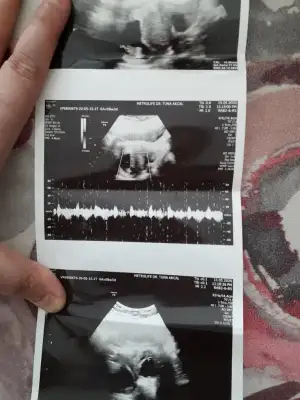

Sadece resmi paylaşın tahminini yazmayın bakalım tutturacammıTeşekkürler2 hafta sonra randevumuz var doktorun tahmini olursa burda resmî ve tahmini de paylaşıcam

![]()

Tamam anlaştıkSadece resmi paylaşın tahminini yazmayın bakalım tutturacammı![]()